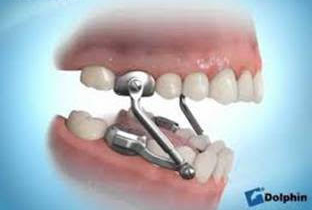

The Herbst appliance is typically used in cases where the overbite is caused by a discrepancy between the size of the upper and lower jaws. The appliance consists of metal rods that are attached to bands placed on the upper and lower molars. The rods are designed to hold the lower jaw forward in a more natural position, which can help reduce the overbite.

One of the advantages of the Herbst appliance is that it can help correct the overbite without requiring the patient to wear headgear. It can also be used in conjunction with other orthodontic appliances, such as braces or aligners, to achieve optimal bite correction and tooth alignment.